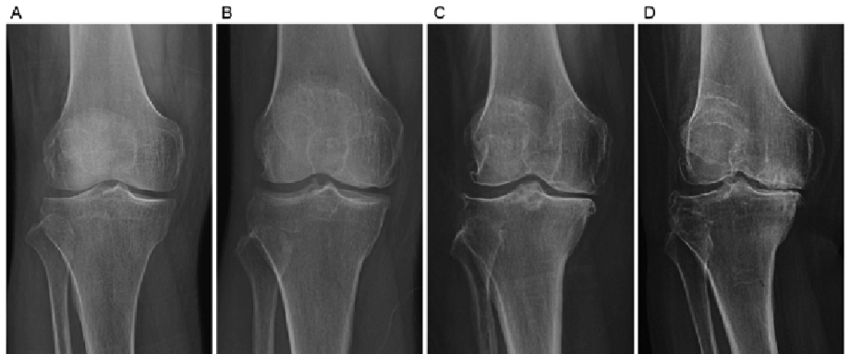

Graus de Artrose (Kellgren–Lawrence)

- Grau 1: Sinais discretos

- Grau 2: Estreitamento leve

- Grau 3: Desgaste moderado

- Grau 4: “Osso com osso” (desgaste avançado)

Diagnóstico da Artrose

O diagnóstico é feito por exame físico e radiografia. Em alguns casos, ultrassom e ressonância ajudam a avaliar estruturas adicionais, como derrame articular e tendões inflamados.